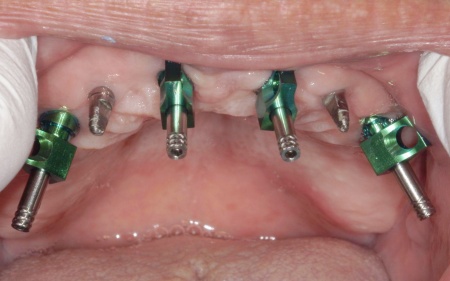

①上の歯7本、右下の奥歯2本を抜歯する。上あごには抜歯と同時に4本のインプラントを埋め、その上に10本分の仮歯を取り付けるオールオンフォーを行う。

インプラントの種類には、あごの骨と結合する力に優れたオステム社のETⅢを採用。インプラントが骨にしっかり定着するまでの間は、通常のインプラントよりも細い暫間インプラントを一時的に併用して仮歯を支える